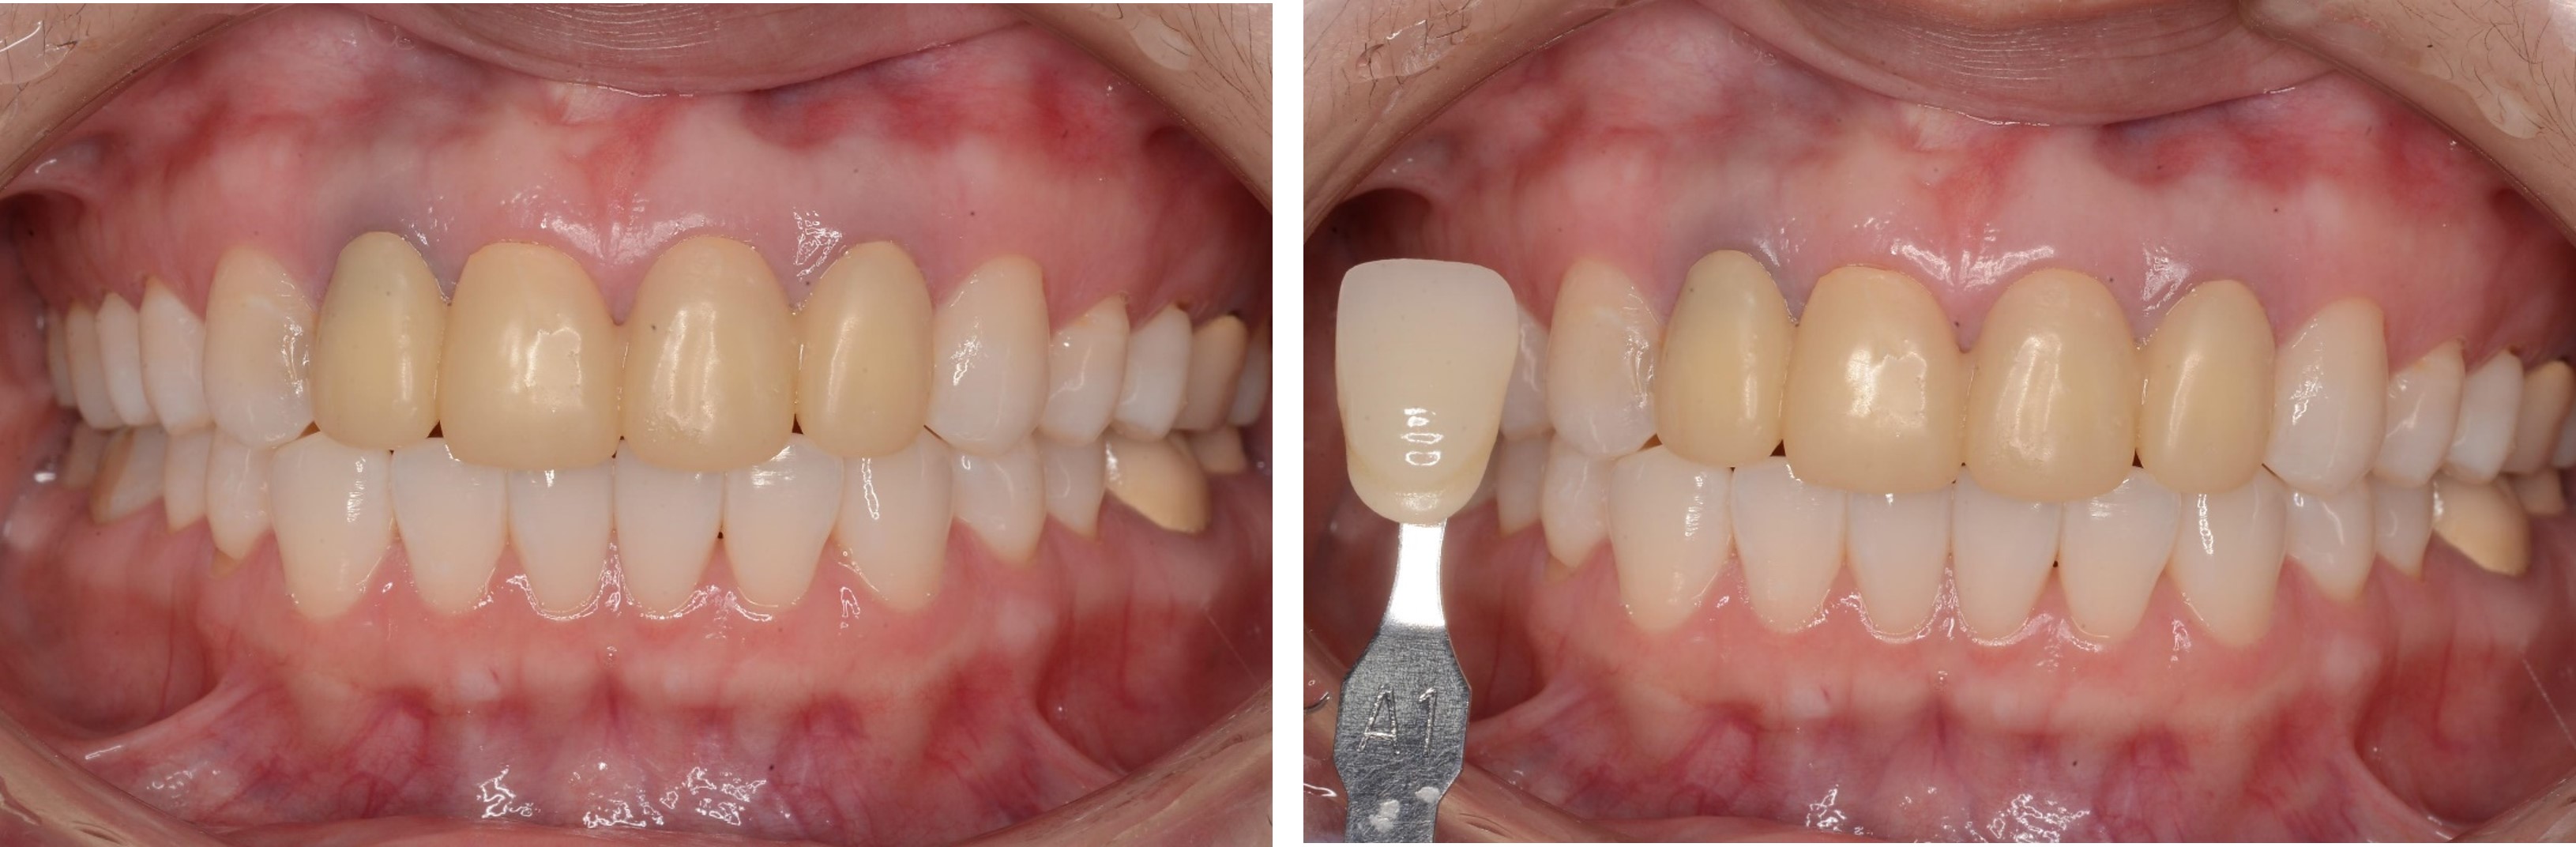

美白前,牙齒預比色-B3

美白前,微笑分析

居家美白1個月後再評估-A1